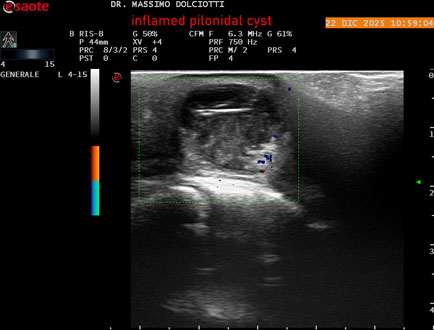

Data inserimento: 24/12/2025

Ecografia del: 22/12/2025

Strumento: Esaote MyLab Eight

Sonda: Lineare Multifrequenza 4-15 MHz

Età Paziente: M 29 anni

Motivazione dell'esame: da 3.giorni dolore, tumefazione ed arrossamento in regione coccigea

Commento all'esame: le immagini ed il video documentano formazione anecogena in sede coccige, delle dimensioni di 24,6 x 18,8 mm, da ricondurre a cisti pilonidale flogosata.

Conclusioni: cisti pilonidale flogosata (inflamed pilonidal cyst).